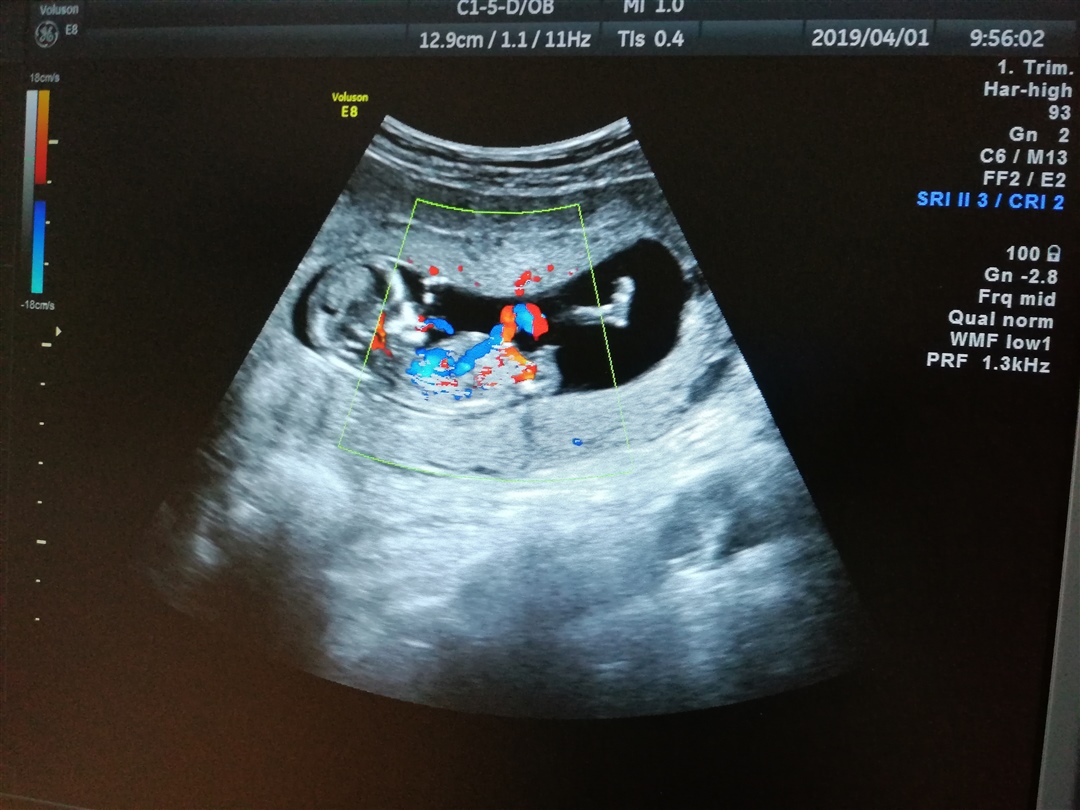

备孕中

孕4周+2天

想佩奇HYGJ4kEh[帖主]:最下面的可以看的出了,只是我们不是专业人士不懂怎么看

孕囊的形状决定不了性别,我的很圆不也是男孩

这个不准吧,我也是茄子,六个月去看的时候说是女孩

想佩奇HYGJ4kEh[帖主]:13周时